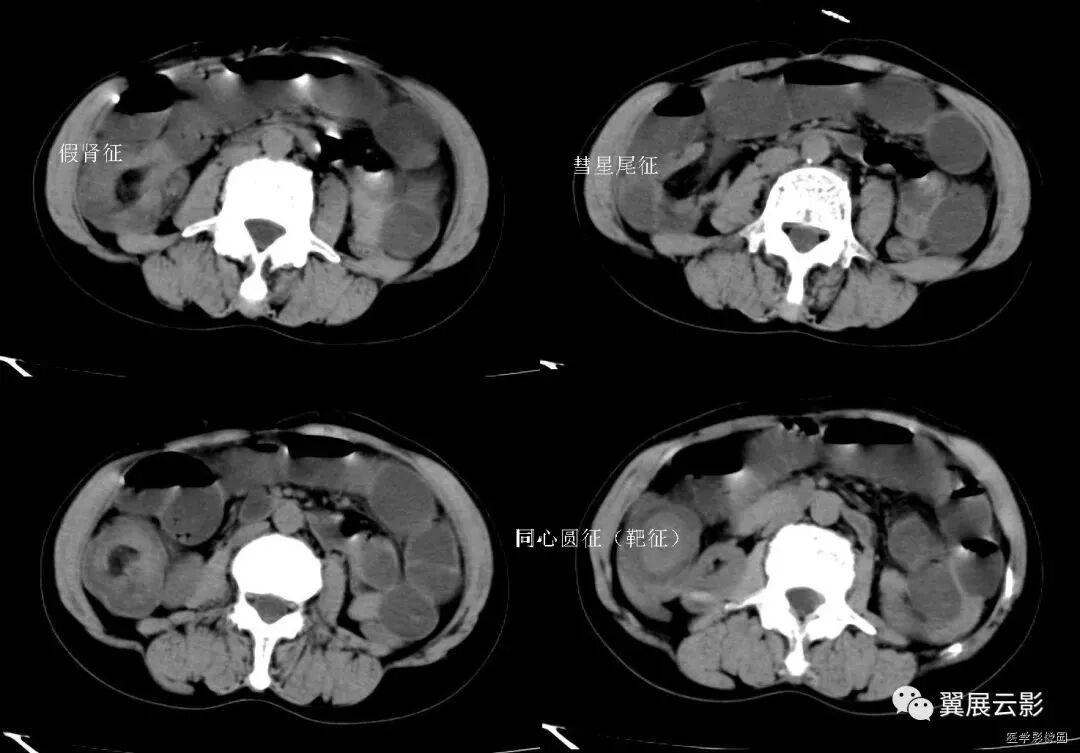

1、靶征(肠套叠)

是肠套叠最常见的特征性CT征像,为肠套叠长轴与CT扫描层面垂直时的表现,反映了套叠的各层肠壁、肠腔及肠系膜间的关系。典型排列为自外向内分别代表鞘部外层肠壁、鞘部肠腔内造影剂、鞘部内层肠壁、偏心性套入部肠系膜、套入部肠壁、套入部肠腔内造影剂。

肠套叠指:一段肠管及与其相连的肠系膜(套入部)被套如其相连的一段长管内(鞘部),导致肠内容物通过阻碍。婴儿由于大肠与小肠管径之比例相差大,故小肠易陷入大肠而被套牢。少数肠套叠可能来自某些器质性病变如美凯尔憩室、肠息肉、异位胰腺小结、血管瘤、异物、复制肠管、淋巴增生、肿瘤、寄生虫等,其中以美克尔憩室最多,过敏性紫斑也常会合并肠套叠,大于2岁的小孩发生肠套叠,一定要考虑到这些病变,大于5岁的病例中,则以淋巴瘤为最多;成人肠套叠小肠多见,常伴发良性病变;结肠型肠套叠则更多由恶性病变继发。良性病变有脂肪瘤、平滑肌瘤、血管瘤、神经纤维瘤、腺瘤样息肉、美克尔憩室、术后粘连以及动力性病变等;恶性病变有转移瘤、腺癌、类癌、淋巴瘤及平滑肌肉瘤等。由于肠套叠长轴与CT扫描层面的角度不同,表现各异。

如扫描层面和迂曲的肠道相平行时,表现为彗星尾征或肾形征:即套叠近端肠系膜血管牵拉聚拢的征象。一般情况下,慧星尾征均与肾型肿块相伴出现。该肾形肿块为套鞘部游离缘与套入部近端肠管及肠系膜的CT斜切面图像,其中游离的套鞘呈弧形围绕套入部,形状若肾轮廓外形,而套入部近端肠管、肠系膜形状若肾蒂。此时,所谓慧星尾征的组成还应包括套入近端肠管。如果套叠的肠管与CT扫描垂直,则呈靶形征,即肿块影表现为圆形或类似环形。通常在肿块内可分辨出层样结构,推测可能是继发于套入部和鞘部间的液体或是肠壁水肿造成密度对比,类似同心圆形;当套入部肠壁显著水肿坏死或套入部肿瘤周围浸润累及肠系膜,肠系膜血管及脂肪、套叠时间较长,套入部系膜血管受挤压时,静脉血液回流障碍,套入部肠壁充血水肿、变硬,形成不完全性肠梗阻,套叠以上肠管蠕动增强,可引起代偿性肠管扩张肥厚,并可见肠系膜连同其血管纠集、扭曲,形成“漩涡征”。

2、靶征(肠壁)

主要见于腹部增强扫描,肠壁表现为三层结构,内层和外层是高密度强化层,两者之间是低密度的中间层。

靶征出现于可导致肠壁黏膜水肿、炎症或两者同时存在的多种肠管病变。其内层代表黏膜层,外层代表固有层和浆膜层,由于对比剂的强化而成高密度,中层的低密度被认为是由于黏膜下层水肿所致。靶征的出现提示黏膜和固有层、浆膜层的充血并伴有黏膜下水肿和炎症。颈静脉注射对比剂后,各层之间的密度差异在动脉早期和门晚期表现最为清楚,如果对比剂注入速度太慢、剂量太少以及延时超过2分钟,此征根本不出现。但是当黏膜下水肿非常严重时,CT平扫也可能出现。如果肠管内充满水而使肠管扩张时,靶征显示更为清楚。

CT扫描时,良性的肠管病变通常表现为肠壁的环形均匀性增厚,厚度从黏膜面到浆膜面一般不超过1公分,根据病因和病变严重程度的不同,偶尔可能超过1公分,但一般在2公分以内。肠壁出现靶征的病变主要见于缺血性肠病、小肠壁内出血、克罗恩病、溃疡性结肠炎、血管性疾病、感染性疾病、放射疾病和门脉高压所致肠黏膜水肿等。靶征并不是一个特异征象,但是在恶性病变中一般不出现此征,只是浸润性直肠癌是一个例外。

所以,一般情况下,靶征的出现,首先要考虑的是肠道的炎症性病变。